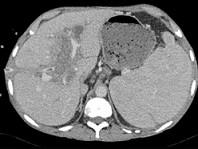

下列图像最可能的诊断是 ( )A.脂肪肝B.肝囊肿C.肝血管瘤D.肝脓肿E.肝炎肝硬化

问题 下列图像最可能的诊断是 ( )

选项 A.脂肪肝 B.肝囊肿 C.肝血管瘤 D.肝脓肿 E.肝炎肝硬化

答案 D